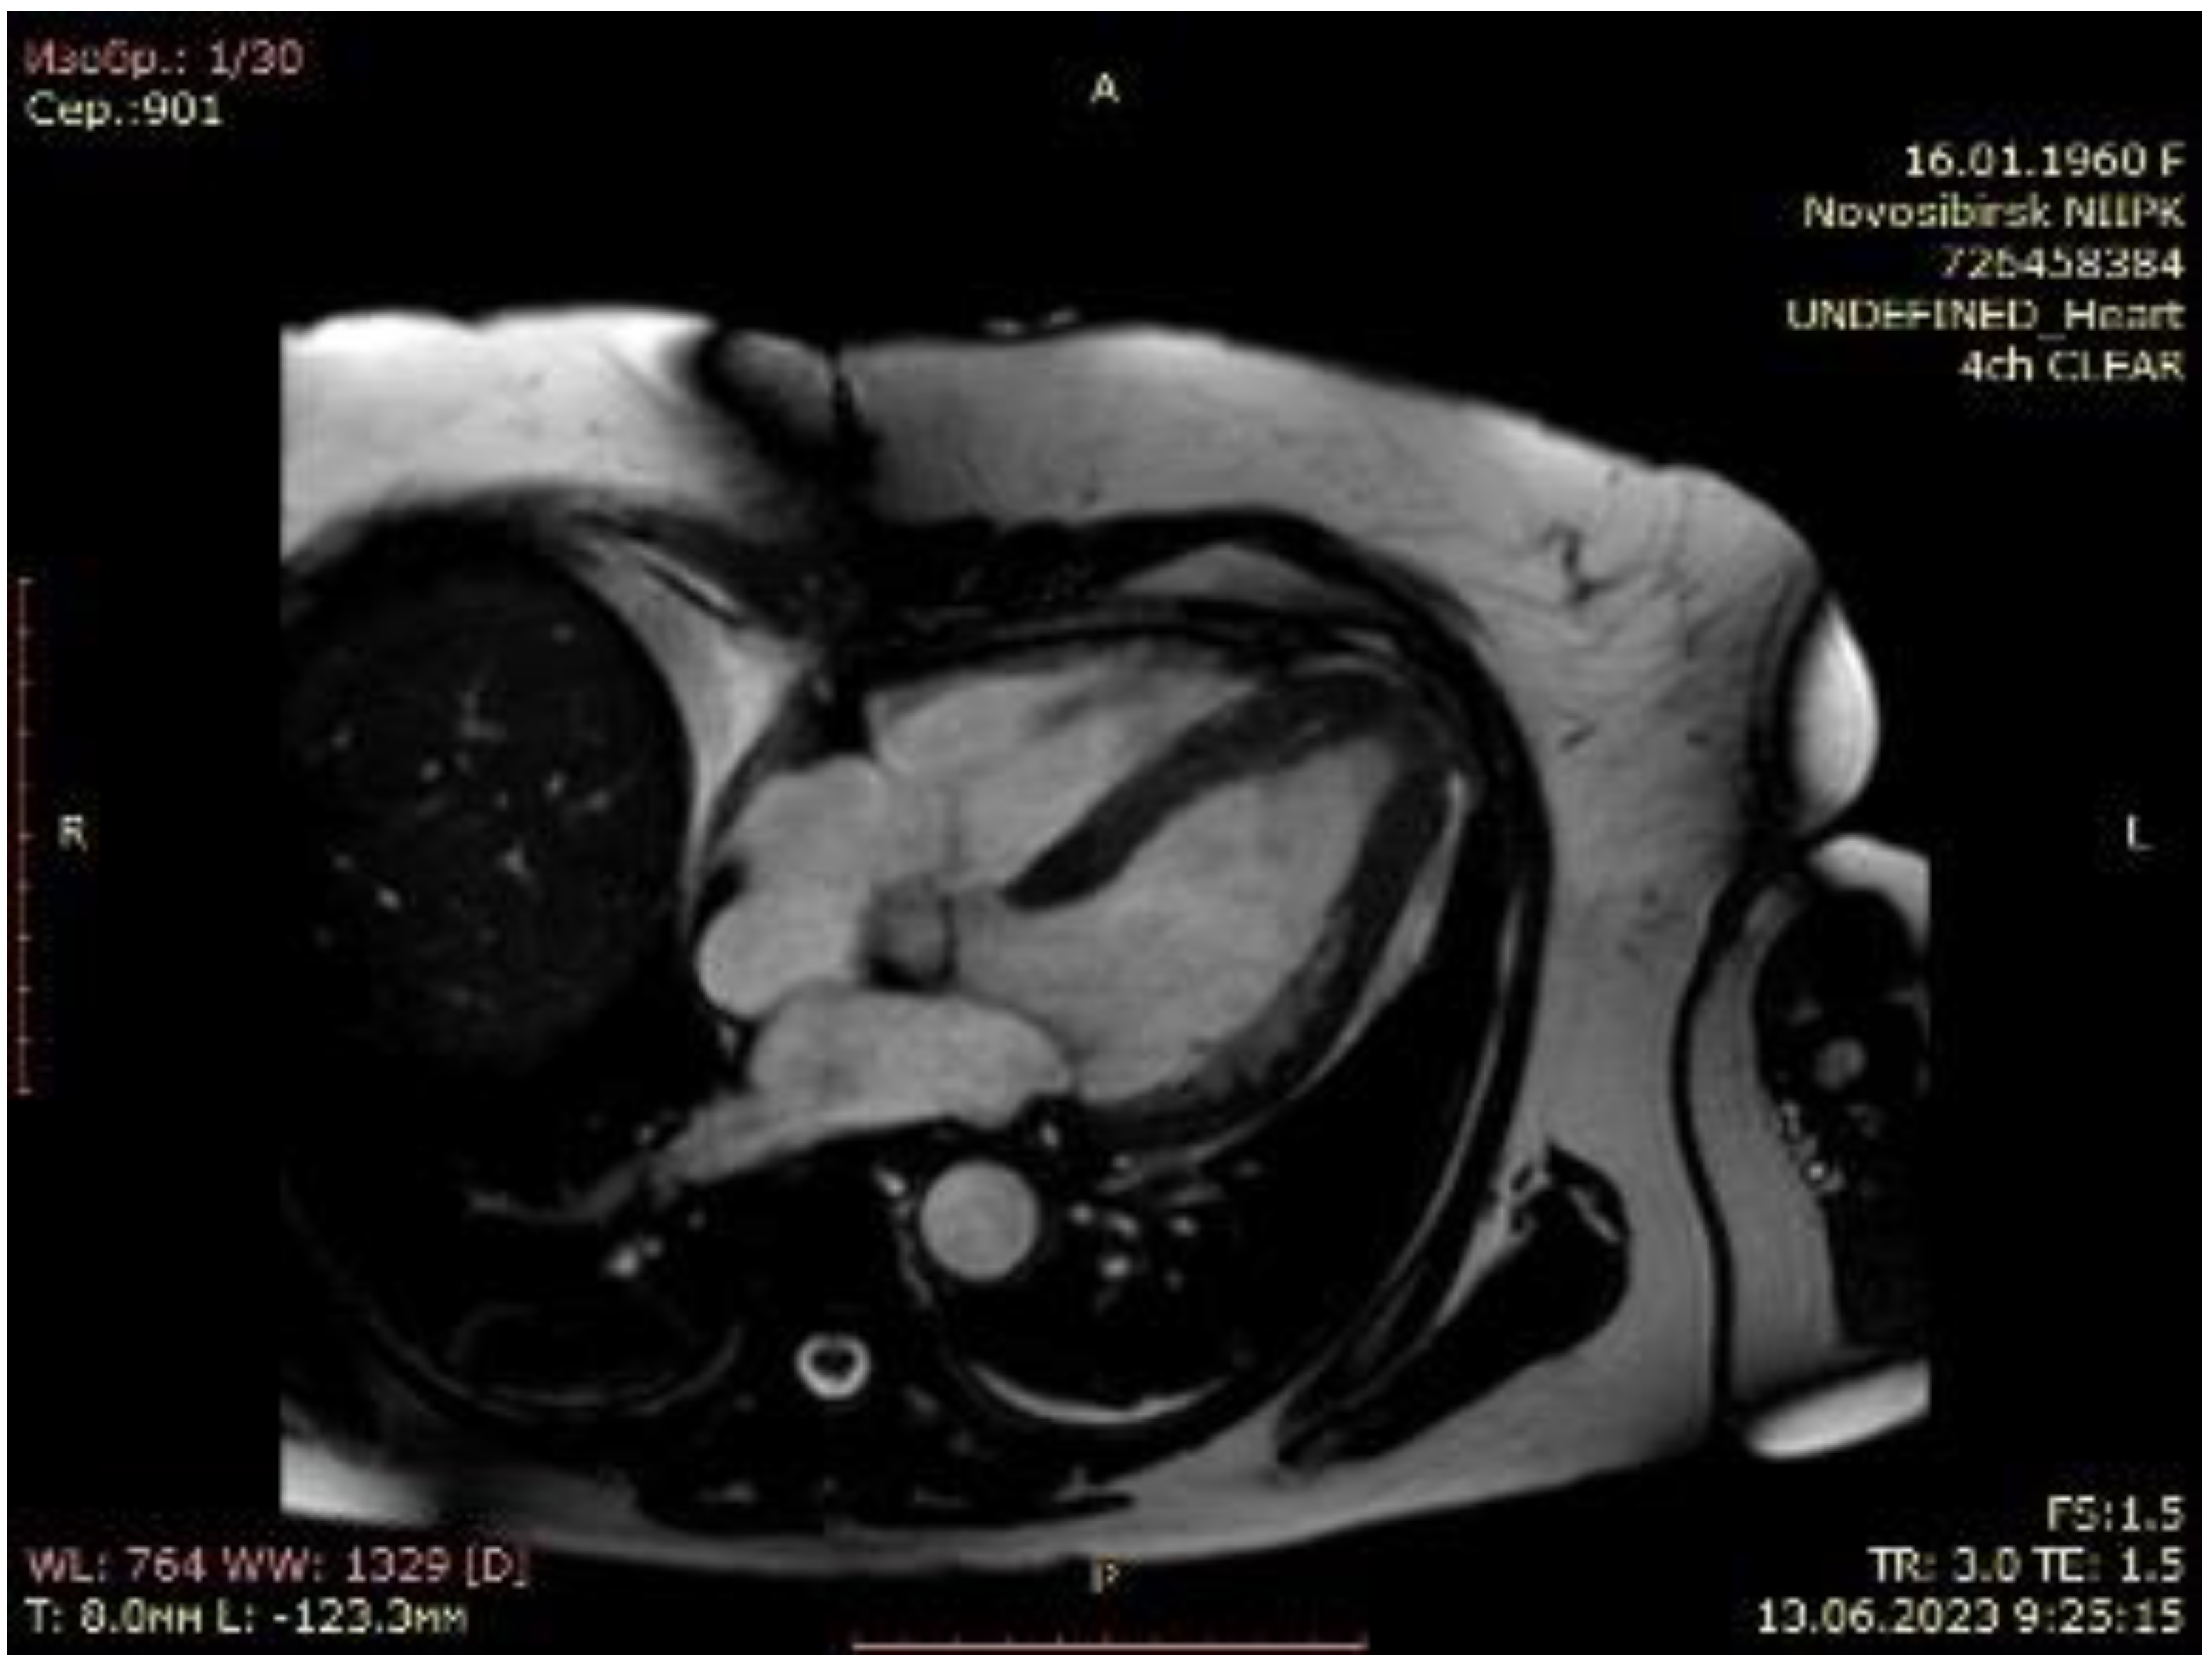

3. Results